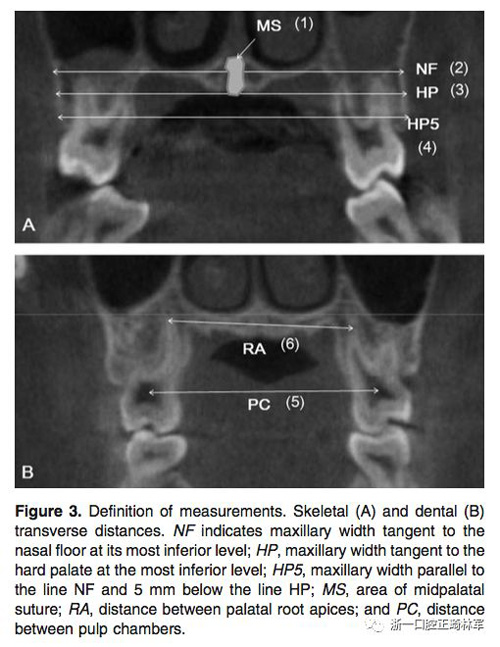

在治療前(T1)和擴(kuò)弓后3個(gè)月(T2)拍攝CBCT,獲得的數(shù)據(jù)由In Vivo Dental(Anatomage,San Jose,Calif)分析。為了在T1和T2階段設(shè)置相同的參考平面,CBCT圖像沿著腭中縫(x平面)定向,平行于腭平面(y平面)并且與鼻底(z平面)相切(Figure 2)。在腭中縫處評估橫向骨骼擴(kuò)張,并在三個(gè)不同的平面進(jìn)行線性測量:鼻底,硬腭和硬腭以下5mm。在根尖和牙冠水平測量橫向牙齒擴(kuò)張(Figure 3)。評估兩側(cè)的牙槽傾斜度,牙長軸,牙齒垂直高度和骨開裂等情況(Figure 4,5)。所有測量均在每個(gè)上頜前磨牙和磨牙區(qū)域進(jìn)行。